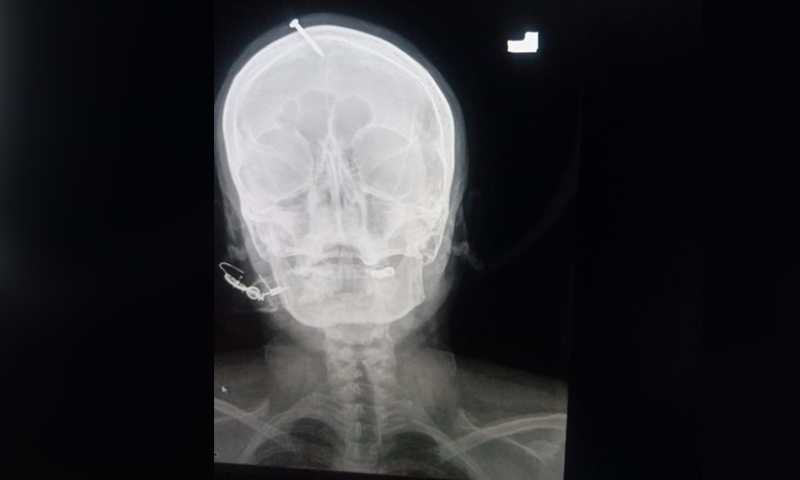

Рентгеновата фотография посочила, че петсантиметровият гвоздей е пробил горната част на челото на дамата. За благополучие той е пропуснал мозъка ѝ. Хан сподели, че за забиването му е употребен чук или различен тежък предмет.